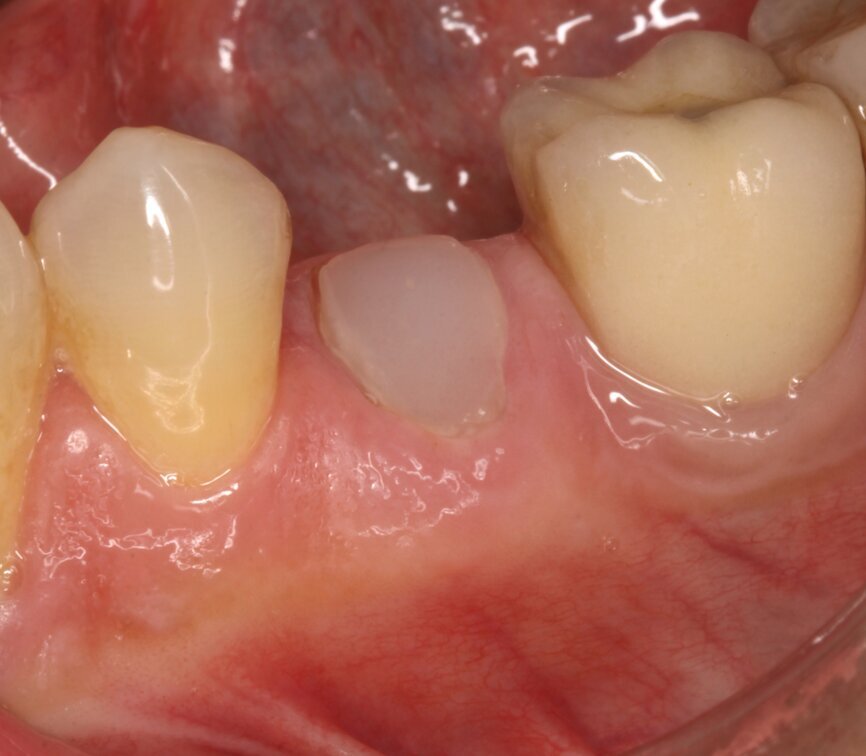

Fig. 10: Clinical situation one year after treatment.

At the one-year follow-up visit, the soft-tissue contours adjacent to the implant restoration and the buccal bone volume and convexity still resembled those adjacent to the natural teeth. Bone levels around the implant appeared stable during radiographic evaluation (Fig. 9). No perceptible loss occurred. The artificial crown had an emergence profile mimetic of that of a natural tooth. At the two-year follow-up visit, the tissue contours looked stable and appeared even to have improved when compared with the one-year follow-up visit (Fig. 10).